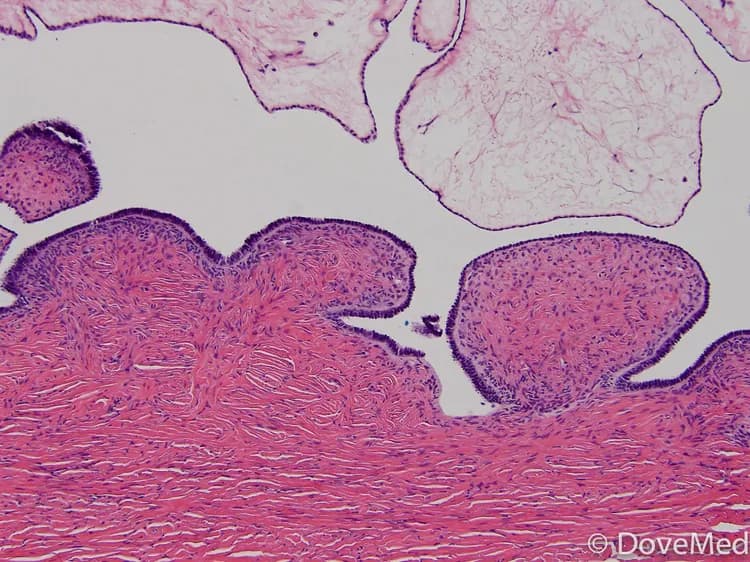

• These tumors originate from the epithelial cells in the ovary and are considered to be of serous type of tumors, based on their appearance under a microscope

A pathologist examines the biopsy under a microscope. After putting together the clinical findings, special studies on tissues (if needed), and the microscope findings, the pathologist arrives at a definitive diagnosis. Sometimes, the pathologist may perform special studies that may include immunohistochemical stains, histochemical stains, molecular testing, and very rarely, electron microscopic studies. Examination of the biopsy under a microscope by a pathologist is considered to be the gold standard in arriving at a conclusive diagnosis.